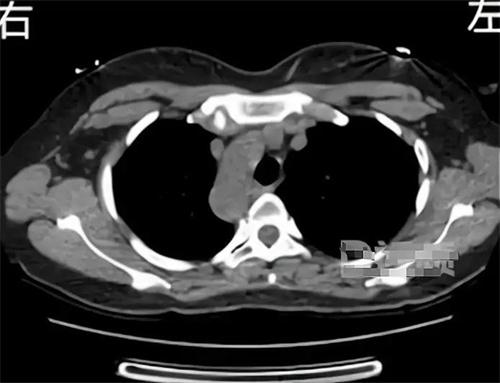

近期,來自陜西寶雞的一名女子在就醫時,發現自己是十分罕見的“鏡面人”,因為五臟六腑全部都長反了。醫生在檢查這位女子身體情況時,發現膽囊、脾臟、肝臟、內臟等,器官與常人完全相反,在醫學領域中被稱為“鏡面人”。“鏡面人”是一種特別罕見的生理現象,發現概率是百萬分之1,盡管這種病例在全球范圍都是比較罕見的,但是“鏡面人”生理功能與正常人來講沒有很大的區別,在生活與工作中都不會有太大的影響。

“鏡面人”并不是第1次出現在醫學文獻中,20世紀70年代就有學者報道過類似的病情,在這類病例中,患者不僅內部器官位置與常人相反,也有一系列的醫學特征,比如心臟大小和形態出現異常,當然這種病例發生幾率比較低,所以很少有人會遇到這樣的情況。對于這類情況的成因醫學領域沒有明確的結論,有學者分析,有可能是與胚胎發育中基因突變有關,也有一部分學者認為,這種病例有可能是一種遺傳疾病,但是不具備傳染性和遺傳性。

鏡面人雖然與常人內部器官位置相反,但不會對身體健康產生過大的影響,在檢查時也要給予更多的關注。就一時需要注意細節在生活中不需要特殊的管理和治療只要保持良好的生活習慣,定期檢查在醫學檢驗時提前告知自己的情況。